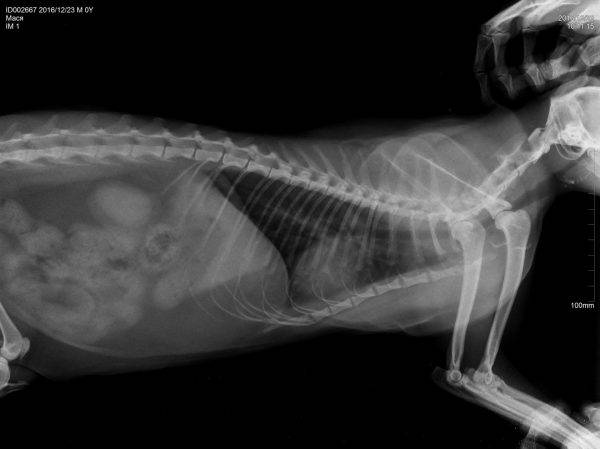

рентген брюшной полости;

Рентген брюшной полости нужен для того, чтобы понять, какие есть отклонения (увеличенный размер или неправильное положение органов, сдавлены ли они и т. д.)

Особенно важно изучение фекалий животного, что позволяет подтвердить или же опровергнуть наличие гельминтов в отделах кишечника. Необходимо проведение анализа кала и для определения наличия опухолевых процессов. Точная диагностика подразумевает ультразвуковые исследования органов брюшной полости и рентгенография, что позволяет получить реальную картину происходящего

Точная диагностика подразумевает ультразвуковые исследования органов брюшной полости и рентгенография, что позволяет получить реальную картину происходящего

Рентген покажет скопление каловых масс, газы и т.п., что позволит диагностировать закупорку, поэтому он является самым информативным методом. В случае, когда в кишечнике присутствуют некоторые мягкие или искусственные материалы, прозрачные для рентгеновского излучения, назначают контрастную рентгенографию с барием, гастрографином (при подозрении на перфорацию кишки), УЗИ или гастроскопию. План лечения кишечной непроходимости у кошки выглядит так: